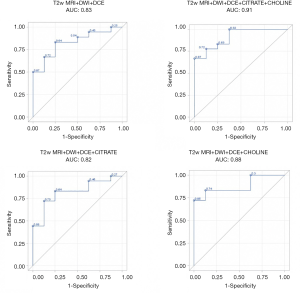

We then analyzed the performance of the MRI topographic sequences in terms of grade T3 histological predictive ability (pT3) in clinical T1 or T2 patients (cT1 or cT2). We then assessed the contribution of mp-MRI and NMR-S sequences to the T2 MRI in identifying post-operative HR. T2w+DWI+DCE MRI models such as T2w+DWI+DCE+cCho, T2w+DWI+DCE+cCit, and T2w+DWI+DCE+cCit+cCho were analyzed with the mean values from healthy and pathological zones, and then with the maximum values from these same zones.

The MRI performance for predicting pT3 stage was described by the sensitivity, specificity, positive predictive value (PPV) and NPV. Receiver operating characteristic (ROC) curves were traced to assess the performance of mp-MRI, with or without the spectroscopy parameters, for predicting pT3 disease or pGS > GS-PB, i.e., an occult HR tumor found by final histology. Different models were compared using their area under the curve (AUC). Analyses were conducted using SAS 9.3 software v. 2011 (SAS Institute, Cary, NC, USA). The chosen statistical significance level was P<0.05.

The results of the predictive models are presented as ROC curves (Figures 4,5).

When looking at mean values, the AUC of T2w+ADC+CWI sequences without NMR-S was smaller than the AUC of the model including NMR-S (0.86 vs. 0.95). The mp-MRI+NMR-S model seemed superior over the mp-MRI model alone for predicting post-operative HR status.

When the spectroscopic analysis took into account a single metabolite, the AUC values for citrate and choline, compared to the model without NMR-S, were 0.88 and 0.91 vs. 0.86, respectively. We then studied the predictive power (PP) of these models for post-operative HR, using our measured maximum parameter values. We found the same results: the model that best predicted post-operative HR status was the one including the mp-MRI + NMR-S (citrate + choline), with an AUC of 0.90 vs. 0.82 with mp-MRI alone.

Here as well, the use of choline alone improved the PP of HR (AUC =0.88 vs. 0.82), whereas citrate alone did not (AUC =0.81). Thus, if NMR-S sequences are performed, citrate and choline levels or choline levels only should be measured.